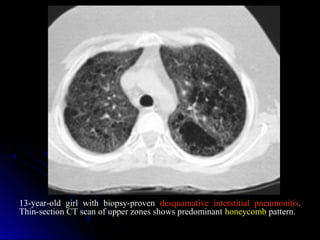

13-year-old girl with biopsy-proven desquamative interstitial pneumonitis.

Thin-section CT scan of upper zones shows predominant honeycomb pattern.